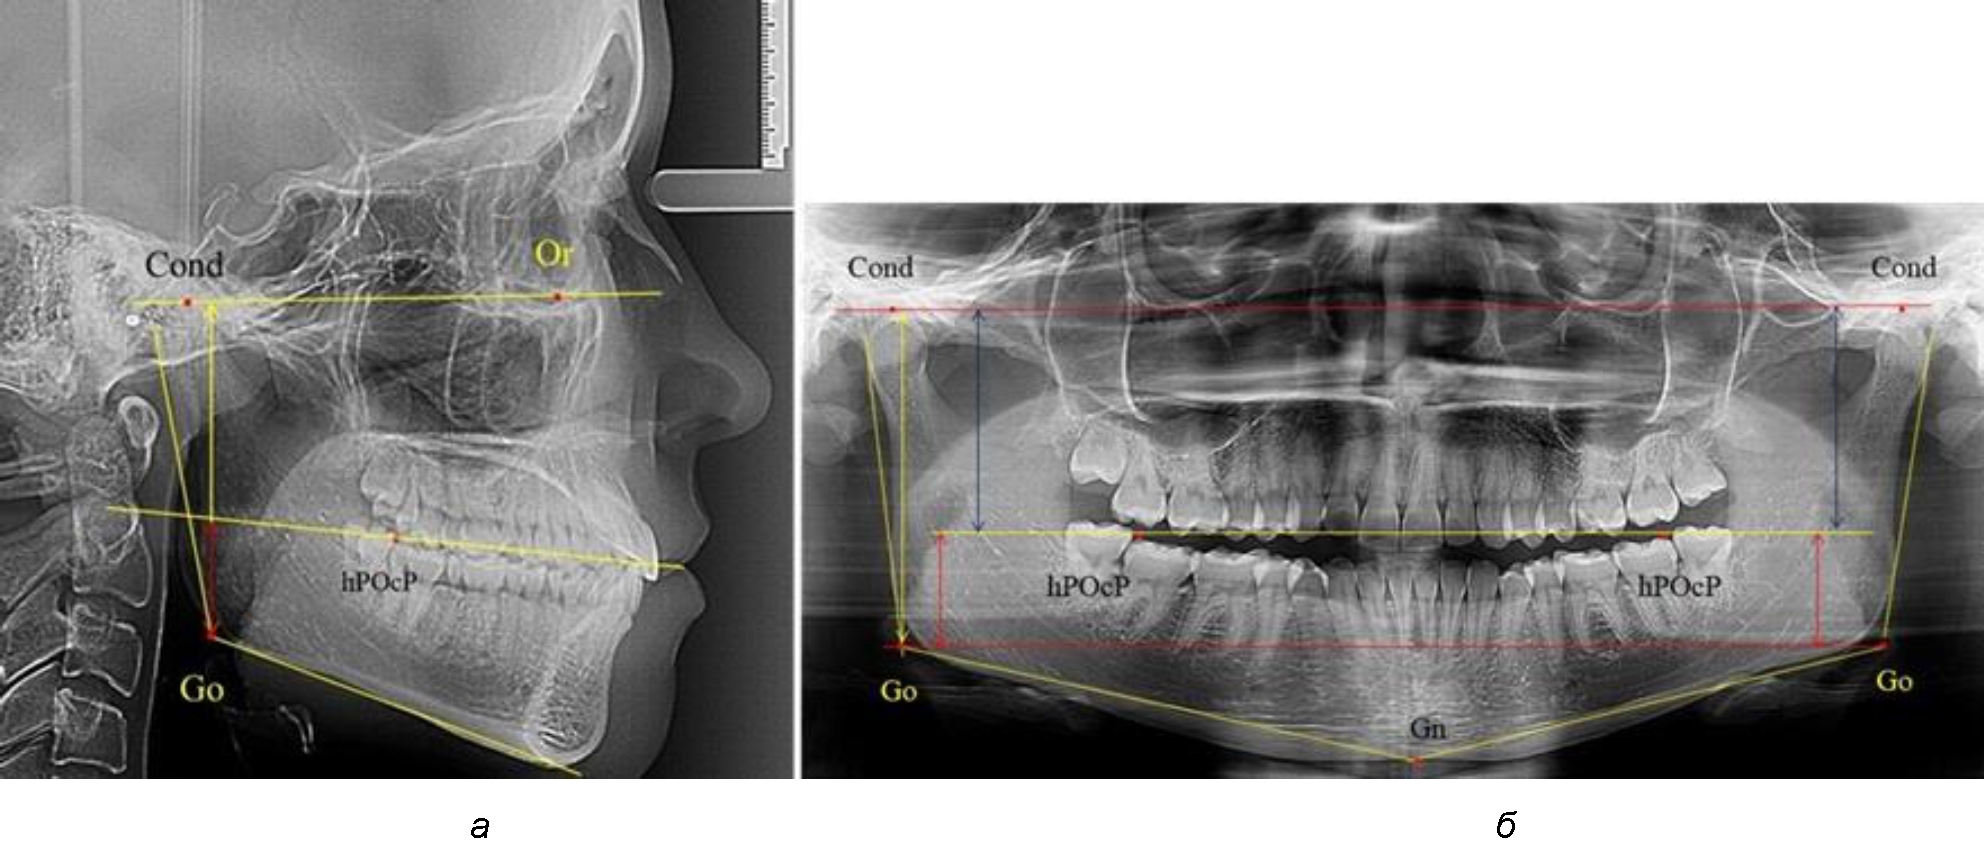

Во 2-ю подгруппу был включен 21 комплект телерентгенограмм и ортопантомограмм [или (28,38 ± 5,24) %], на которых средняя величина отношения верхней части ветви к нижней составляла 1,63 ± 0,03, что было достоверно меньше показателя, полученного по группе в среднем и в 1-й подгруппе.

Визуально параметры ветви отличались от первой группы (рис. 3).

Рис. 3. ОПТГ пациента 2-й группы с уменьшенным коэффициентом соотношения частей ветви нижней челюсти

Высота ветви составляла (62,75 ± 1,42) мм и достоверных различий по этому показателю не отмечено. Максимальная высота была 73 мм, а минимальная – 55 мм. Высота верхней части составляла (38,81 ± 0,76) мм, что было достоверно меньше, чем у людей 1-й подгруппы.

В то же время высота нижнего отдела ветви была (23,94 ± 0,73) мм, и показатель отличался в большую сторону по сравнению с аналогичным размеров в 1-й подгруппе.